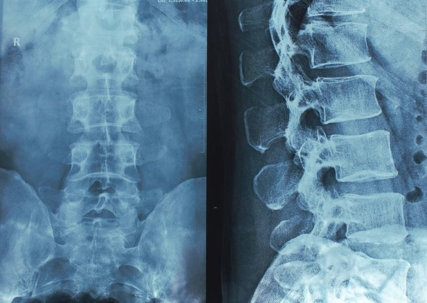

Car Accidents Can Cause Spinal Cord Injuries

Xray of a Human Spine

A car accident can lead to catastrophic injury, and one of the most common injuries is spinal cord damage. Catastrophic injuries are life-altering by nature, and few are more life-altering than spinal cord injuries. They are characterized by pain, loss of mobility, and exorbitant medical expenses. Not all vehicle crashes are the same, and while some minor collisions can result in unfortunate spinal damage, these injuries are more common in high-velocity crashes.